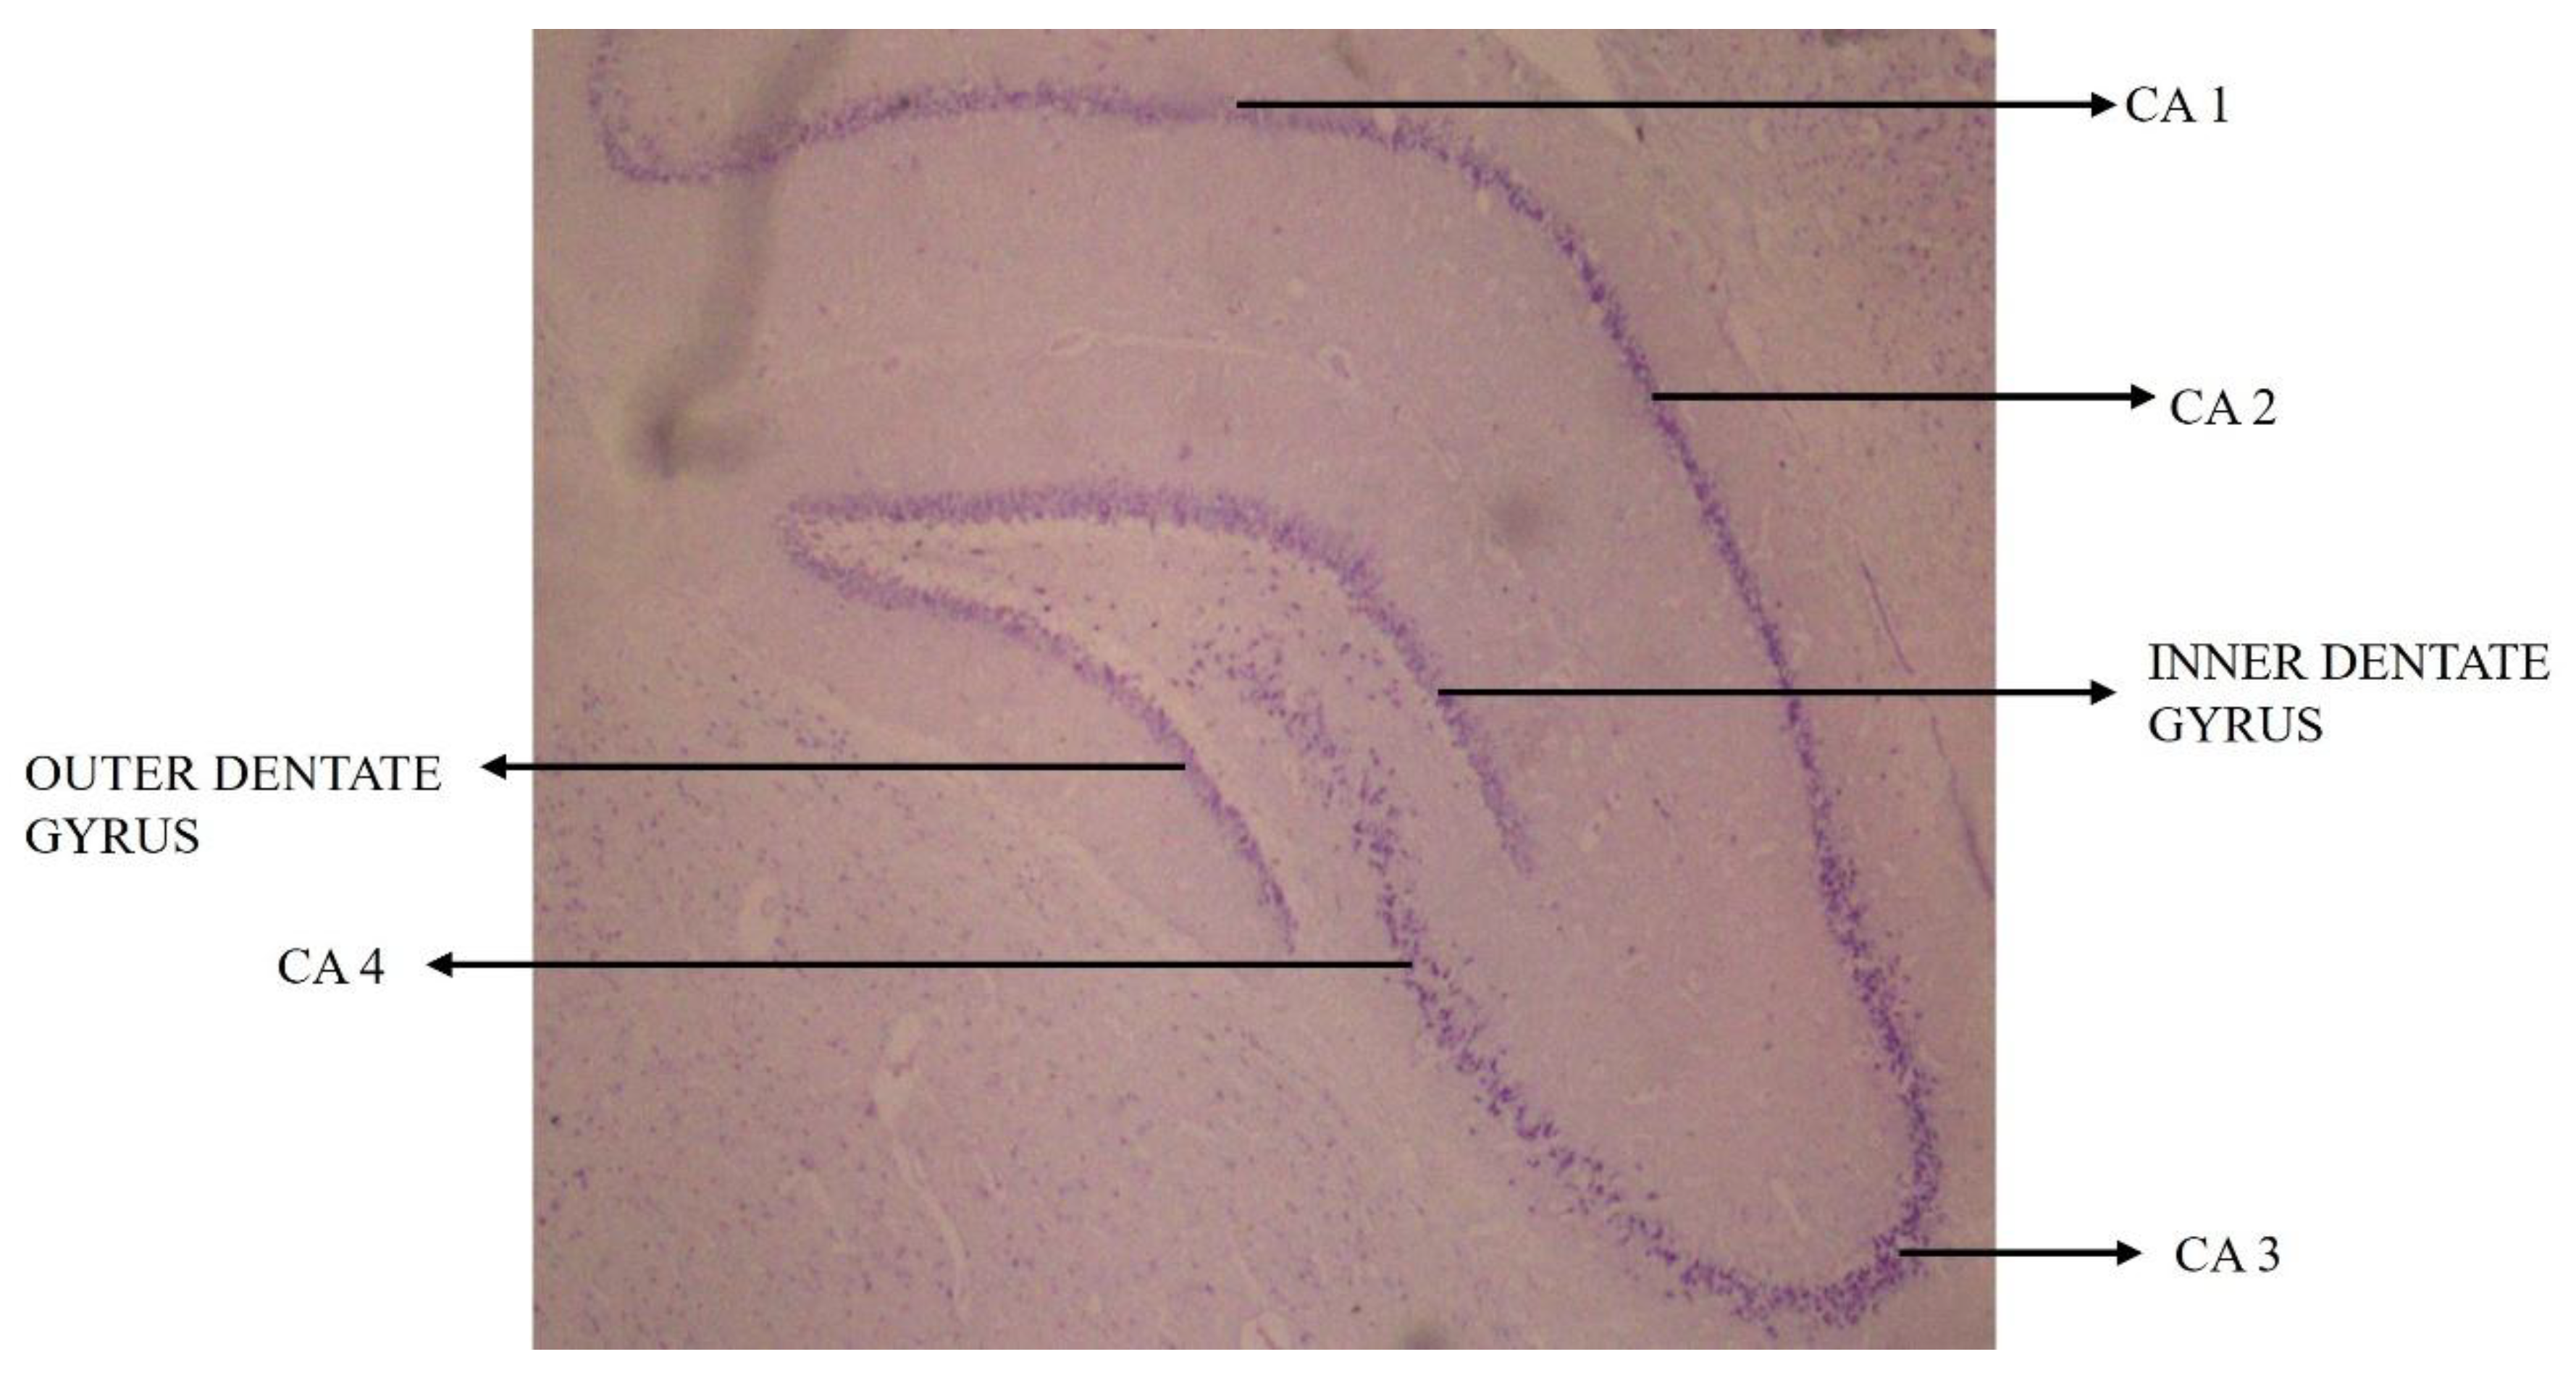

| G.S. Prabhu [20] | 2021 | Sprague Dawley rats | Long-term HFD feed resulted in significant reduction in number of surviving neural cells in hippocampus. |

| G.S. Prabhu [30] | 2021 | Sprague Dawley rats | HFD supplement from young age throughout childhood, increased the TG, cholesterol and LDL levels, thus resulting in significant reduction in surviving neural cells in CA3 subregion of hippocampus. |